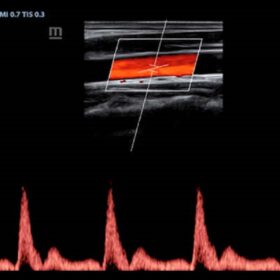

Ultrasound Mindray Z60 – Image Gallery